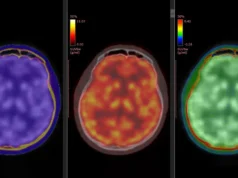

Os animais de estimação da Tau permitem que os pesquisadores imaginem proteínas anormais no cérebro, que contribuem para a doença de Alzheimer, conhecida como Tau, um rastreador radioativo especial que destaca as regiões da Tau. Com essas varreduras, os pesquisadores podem estabelecer pontos de corte tau, usados para determinar um novo tipo de biome trabalho que uma varredura mostra muita proteína tau no cérebro para sugerir que a doença de Alzheimer ou possíveis sintomas iniciais de condições relacionadas. Esse novo benchmark pode finalmente explicar a maneira como os médicos explicam as varreduras de PET tau e podem identificar melhor quem corre o risco de DA.

A equipe usou um novo traçador de imagem chamado 18F-PI-2620 para medir o acúmulo de proteínas Tau no cérebro. Eles descobriram que, quando a região profunda do cérebro – a camada do lobo temporal médio excede um marginal específico, indica fortemente a fraqueza cognitiva do AD.

“Embora nossa pesquisa conecte o lobo temporal médio à fraqueza cognitiva, o uso de 18F-PI-2620 estabelece um ponto de corte na região, um passo importante para definir a positividade da tau para as aplicações de pesquisa e clínica, o determinante social da doença de Alzheimer”, USC Gruce Gruce Gruce Gruce. Inquilino diz.